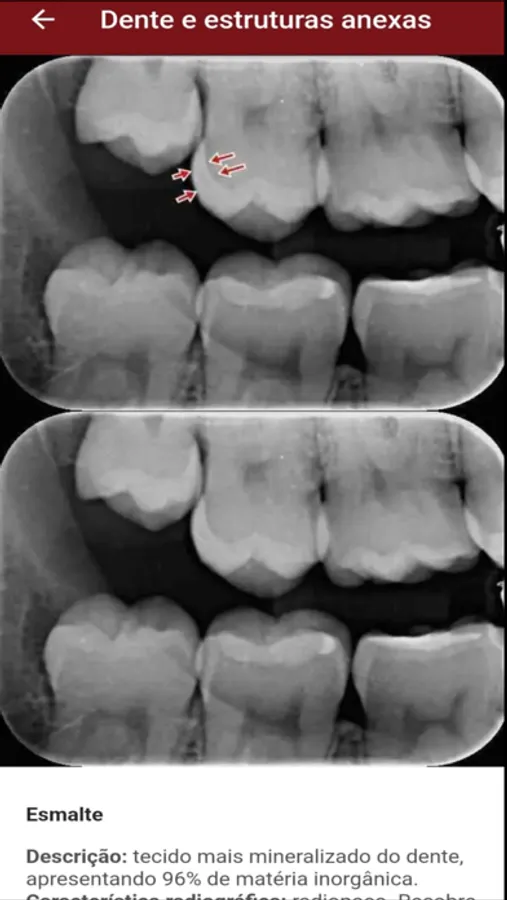

• Patologia